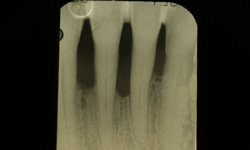

Prima

Dopo (controllo ad 1 anno)

Caso clinico di difetto parodontale severo , trattato con intervento di chirurgia parodontale rigenerativa